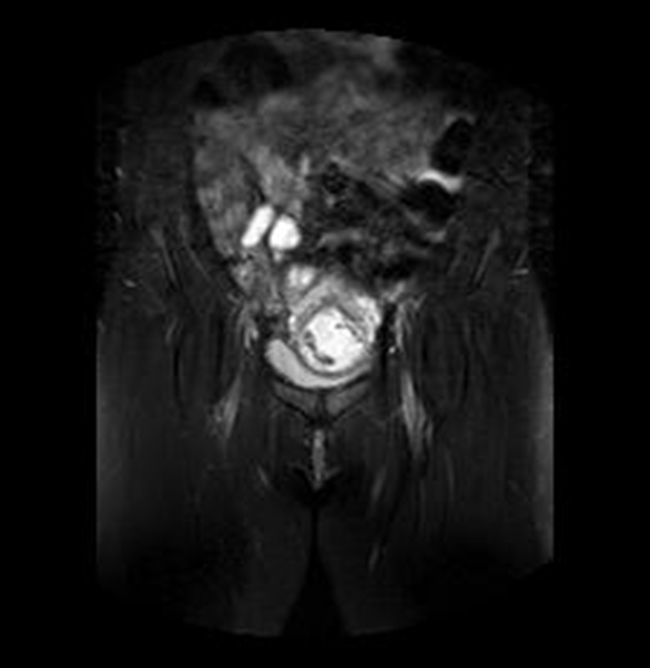

A la paciente se le realizó una prueba en sangre para cuantificar la fracción beta de la gonadotrofina coriónica humana (Abbott Laboratories. Architect.B-hCG Total), que se reportó en 31.819 mUI/ml. También se le tomó una ecografía endovaginal (Toshiba-Xario XG) que mostró la presencia de útero con medidas de 72 × 52 × 54 mm con un cuello de 35 mm con orificio interno cerrado. El endometrio midió 18 mm, sin evidencia de saco gestacional intrauterino y en la región ístmica y cervical, por debajo de las arterias uterinas, se encontró un saco gestacional de 30 mm con presencia de embrión único de 20,6 mm sin presencia de actividad cardiaca fetal (figuras 1 a 4).

Se realizó una RNM (Philips 1.5 Tesla) que permitió confirmar el diagnóstico de EEC (figuras 5 a 8).